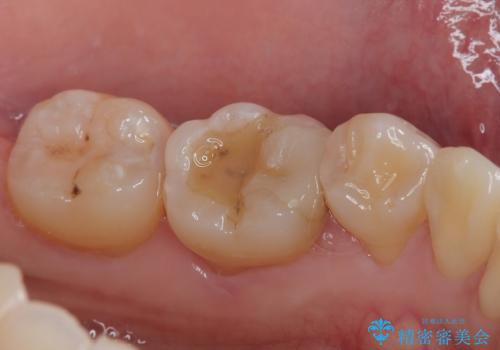

- 他院で保険の詰め物を行い、割れたためやり替えたいとのことで来院された患者様です。

セラミックの詰め物(セラミックインレー)とセラミックにプラスチックを混ぜた詰め物(ハイブリッドインレー)の二種類のメリット、デメリットを説明したうえで、患者様のご希望でハイブリッドインレーで治療をしていくことになりました。

拡大鏡視野下で、保険の詰め物、虫歯の除去を行い、ハイブリッドインレーに適した形に整えました。